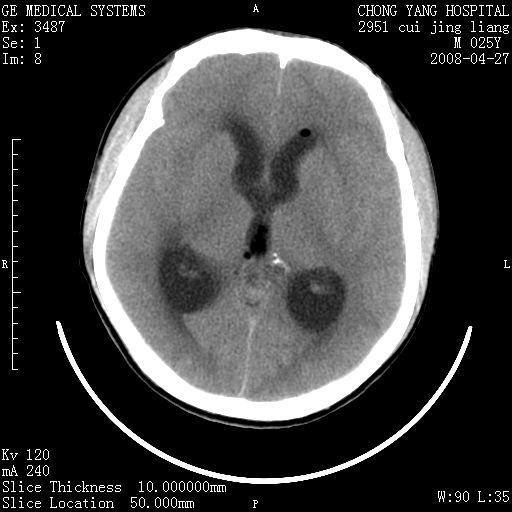

以下是引用余辉在2008-4-27 17:08:00的发言:[br]支持考虑松果体区畸胎瘤伴梗阻性脑积水,左侧室前角还有脂液滴?

以下是引用王仕学在2008-4-27 16:25:00的发言:[br]软组织肿块+脂肪球,考虑松果体区畸胎瘤可能性大。

以下是引用随光逐影在2008-4-27 20:13:00的发言:[br]1)考虑为:第三脑室后部、松果体区畸胎瘤。2)脑积水(梗阻性)。

以下是引用jinguoji在2008-4-27 23:41:00的发言:[br]考虑松果体区肿瘤引起梗阻性脑积水。